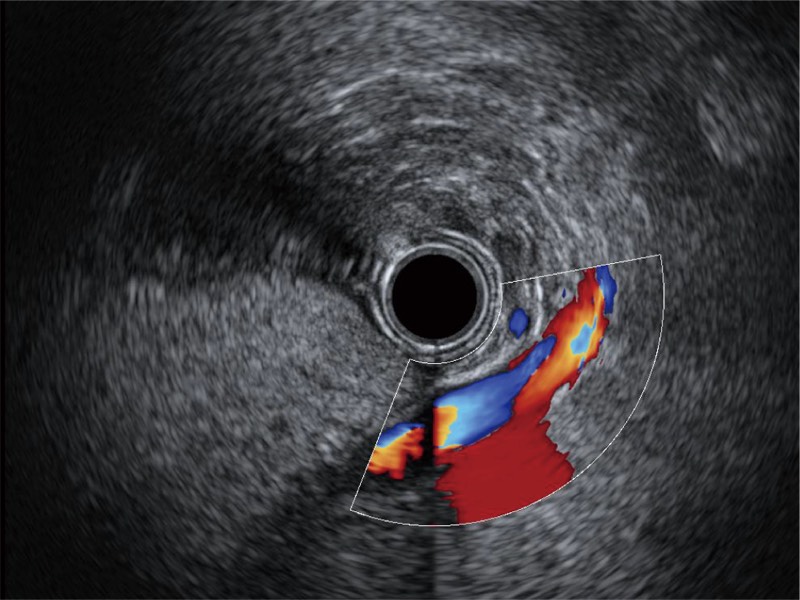

• 食管内间质瘤清晰显像

• 清晰显示胆总管及周围血管分布